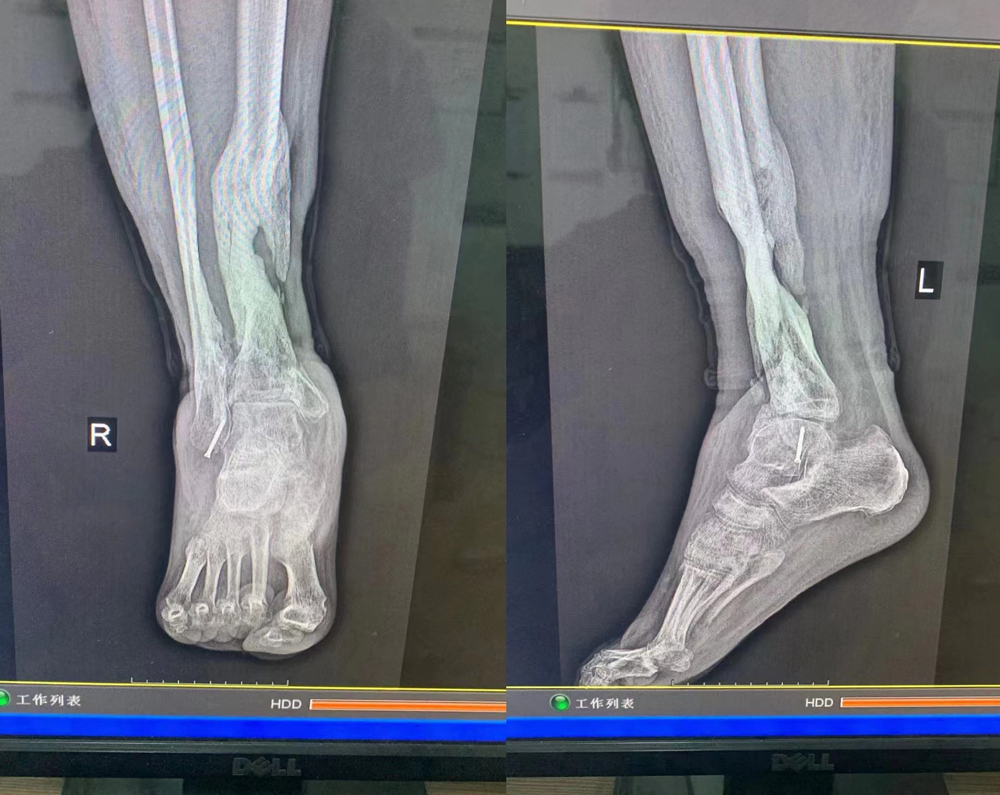

山西省洪洞县患者随先生,2021年2月因车祸造成右小腿胫腓骨开放性粉碎型骨折,在山医xx手术清创整复骨折钢板螺丝钉内固定,术后感染化脓,钢板,骨头外露,左小腿、左脚高度肿胀痛疼,肌腱腐烂、骨头发黑,流污浊脓液,恶臭难闻,其他医院建议截肢,患者及家人又到北京xxx医院、xx医院等均建议截肢…后经人介绍2021年4月来我院,手术取除内固定、取除死骨(右胫骨下段几乎完全取除)、清创病灶,内服、外敷我院研制的系列特效药物等治疗5月余,患者右小腿肿痛消失,伤口愈合痊愈出院,当时告诉患者,因为骨头感染严重,取的骨头太多,需要一年后植骨治疗,没想到患者出院后,坚持服用我院研制的参鹿填髓丸、舒筋接骨丸、海马壮骨胶囊等,患处外敷骨康膏等,骨质破坏修复,骨痂大量生长,已经重新站立起来了,可以自由行走了!